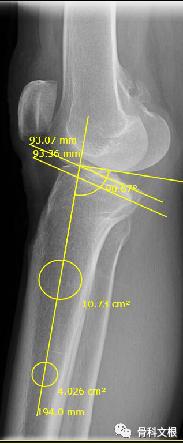

经检查,张阿姨右膝关节轻度内翻畸形,内侧触痛明显,活动时疼痛症状加重,右膝旋转挤压实验阴性,前后抽屉实验及侧方应力实验阴性,右膝屈曲110度,伸直0度,右下肢感觉正常,血运正常。随后诊断为右膝骨性关节炎。

文根主任查看病人后,结合病人症状,查体及辅助检查。内侧间隙明显变窄,力线偏离,考虑行关节置换较早,后期需要翻修治疗,且费用较高,文根主任决定为患者行胫骨高位截骨矫形手术治疗。